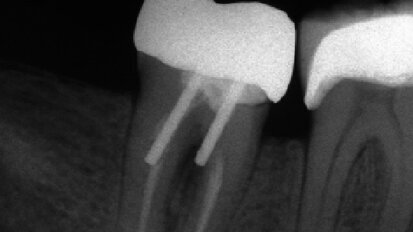

Reendodontické ošetrenie dolného molára

Endodoncia je predovšetkým o zachovávaní prirodzených zubných tkanív. Nie je lepší ...

Hlavní zásady, které zvyšují úspěšnost rekonstrukce endodonticky ošetřených zubů

Rekonstrukce endodonticky ošetřených zubů a jejich zachování po zbytek života zůstává výzvou. Na ...

Odpovědi na běžné klinické otázky z endodoncie – Vysvětlení tří základních konceptů

Lékaři zabývající se endodoncií mají řadu otázek týkajících se klinických ...